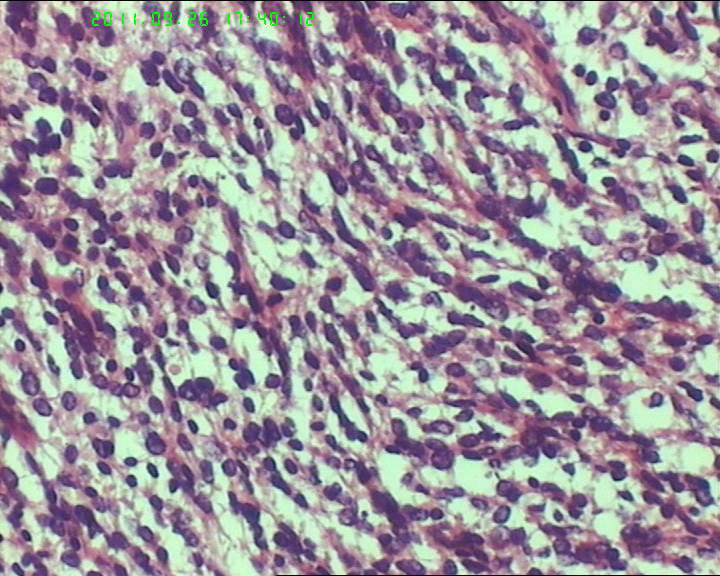

灰白不整形肿物一个,大小18*15*9cm,表面结节状,包膜完整,切面灰白,中央可见坏死区,质软,范围5*4cm。其余切面多彩 部分半透明状 质中。

鉴别诊断排排队:1、GIST,2、MPNST,3、去分化脂肪肉瘤,4、恶性间皮瘤,5、恶性SFT,6、平肉

主要考虑前二者。CD34,CD117,S-100,BCL-2,SMA, D2-40,CR, VIM. 结果如何?请楼主揭谜底吧。